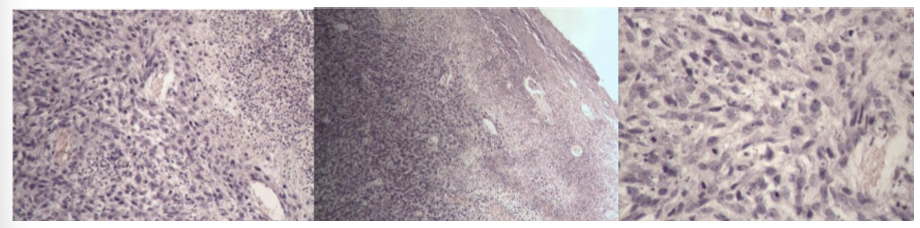

Leucosis lymphadenoidea hepatis - lymphosarcoma

one end of liver → basophilic stained tumor tissue formed by slightly differentiated lymphocytes